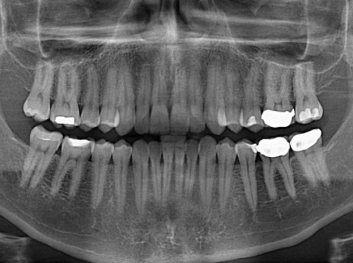

損壞的牙齒如何自我修復(fù)?近日,來(lái)自哈佛大學(xué)和諾丁漢大學(xué)的研究人員研發(fā)了能夠刺激牙齒干細(xì)胞再生的新型生物材料,而這種新材料研發(fā)成功的背后,正源于他們對(duì)牙齒如何實(shí)現(xiàn)自我修復(fù)這個(gè)課題的不斷探索。

據(jù)美國(guó)期刊《大眾科學(xué)(Popular Science)》報(bào)道,此種新型生物材料,不僅可以有效地取代傳統(tǒng)補(bǔ)牙填充物,刺激牙齒干細(xì)胞再生,患者也有望無(wú)需再接受根管治療,使蛀牙患者免除牙根感染或牙髓壞死的苦惱,一個(gè)全新的牙齒治療時(shí)代即將來(lái)臨。

Adam Celiz,是來(lái)自諾丁漢大學(xué)的研究人員,他和同事開(kāi)發(fā)的這種新型合成生物材料,能刺激干細(xì)胞在牙髓部的生長(zhǎng)。與普通材料一樣,這種合成材料被填充到牙齒并用UV光硬化。

在體外測(cè)試中,材料刺激干細(xì)胞進(jìn)入牙本質(zhì)的增殖和分化速度,促進(jìn)形成牙齒骨組織。研究人員認(rèn)為,一旦材料在受損牙齒中應(yīng)用,這些干細(xì)胞可以自動(dòng)修復(fù)來(lái)自填充物上的損壞。在本質(zhì)上,該生物材料將使牙齒自愈。

在未來(lái),Adam Celiz說(shuō),可再生材料能制成各種填充物以便受損牙齒的自身治愈,降低補(bǔ)牙失敗率,甚至?xí)蟛糠秩藢?duì)根管治療的需要。